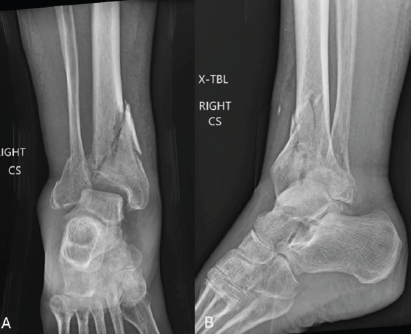

An Uncommon Case of Bilateral Ankle and Foot Injury in a Pediatric Patient Leading to Bilateral Talus Fracture

Laxman Choudhary , Amandeep Bains , Aakarsh Aggarwal , Nitesh Gahlot , Akshant Chandel , Aryan Mechu